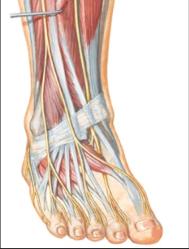

The red pins in the bottom picture point out the nerves in the top pictures. As you can see different nerves travel to different parts of the foot, top, bottom, sides and toes. By isolating the exact location of neuropathy we can isolate the nerve involved.

Diagrams courtesy of Netter's Anatomy